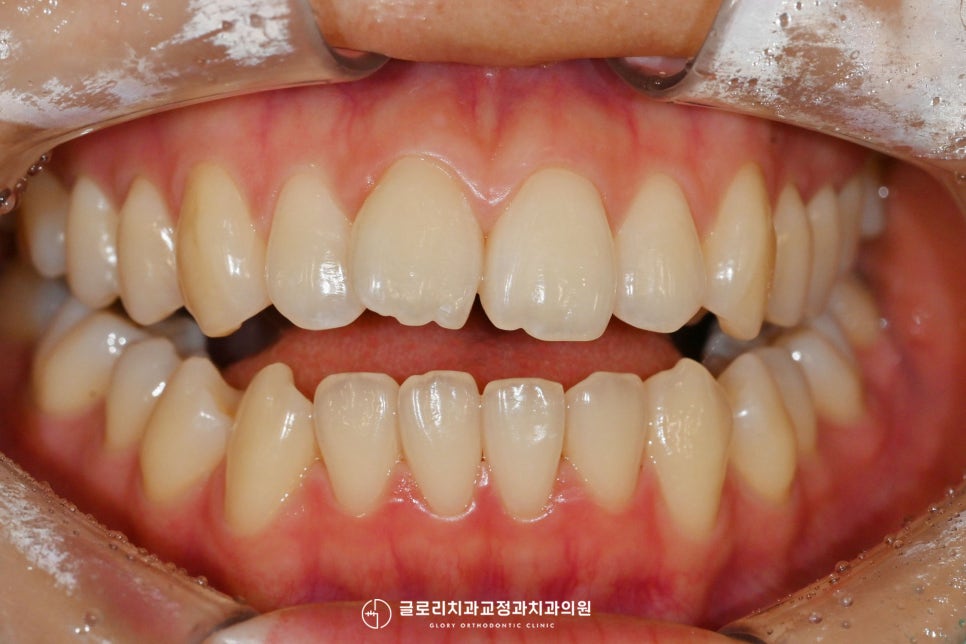

치료 기간은 4개월이 소요되었습니다.

생각보다 빠르게 완료가 되었죠^^

완료된 사진을 보시면

처음의 문제들이 잘 해결되었는데요.

틀어져 보였던 전치부가

이제는 가지런히 정렬이 되었고,

보기에도 더 예뻐진 느낌이 듭니다.

완료된 후 환자께서도

이렇게 빠르게 완료될 줄 몰랐다며

바뀐 모습도 마음에 드신다고

연신 말씀해 주셨는데요^^

최종 완료는 입천장 쪽으로

유지 장치를 제작해 붙이는 것으로

도와드렸는데요.

개선을 진행하실 때처럼

부착은 윗니에만 시행을 했습니다.

치료 기간: 24.03.07~24.07.05